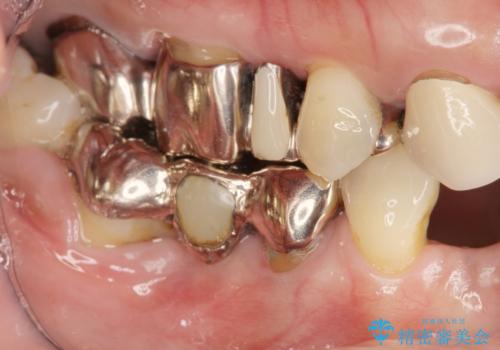

![[ 破折し大きく吸収した歯槽骨 ] 他院では難しいと言われたインプラント治療の症例 治療前](https://seimitsushinbi.jp/wp/wp-content/uploads/2024/10/073ce5e06775df372887a513b05b34d0-500x350.jpg?v=1729760111)

![[ 破折し大きく吸収した歯槽骨 ] 他院では難しいと言われたインプラント治療の症例 治療後](https://seimitsushinbi.jp/wp/wp-content/uploads/2024/10/7e00d9287463e80cbc3d4b87784b3d86-500x350.jpg?v=1729760167)